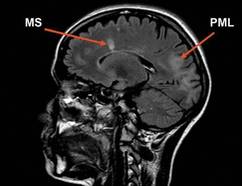

Courtesy Biogen Idec

Sagittal FLAIR (Fluid Attenuated Inversion Recovery) MR image of a patient with MS and PML.